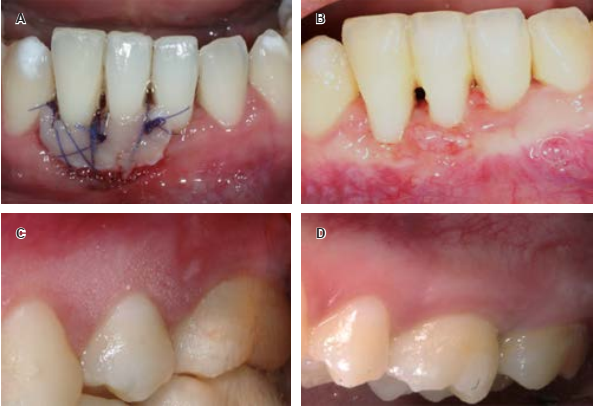

The placement of a wire splint with composite in teeth 4.1 and 4.2 initiated the procedure. After infiltrating local anesthesia (2% lidocaine with epinephrine 1:80,000) the exposed surfaces of the affected incisor roots were planned with a «McCall 13- 14S» curette. At the recipient site, a horizontal incision apical to the keratinized tissue was made with the help of a «Hu-Friedy MB64» micro scalpel (Figure 2A). The lower labial frenum was liberated to release tension and avoid graft from shifting.

Figure 2 A) Incision at the recipient site. A partial thickness flap was designed with a a «Hu-Friedy MB64» micro scalpel in order to create a vascular bed. B) Donor site, located on the buccal aspect of tooth 1.6 after extraction of the partially thick tissue for graftingthrough a rectangular-shaped incision, chosen for this purpose. The integrity of the gingival margin was preserved; C) The graft was de-epithelialized after extraction, measuring 14 × 5 × 1 mm. D) Minimally invasive free gingival graft placed on the recipient site.

Two horizontal incisions were made at the donor site (the buccal aspect of 1.6) using a «15C» scalpel blade. The first one was made 2 mm apical to the free gingival margin. This incision was then connected to a second one, wich was located slightly coronal to the mucogingival junction (Figure 2B), thus giving the graft a rectangular shape (14 × 5 × 1 mm). The graft was then harvested from the donor site, trimmed (Figure 2C), placed on the recipient connective bed and sutured with nylon thread, 6-0 non-resorbable «Atramat»® suture (Figures 2D and 3A).

Figure 3 A) The graft was sutured with nylon thread, 6-0 non-resorbable «Atramat» suture, using a suspensory technique. B) Recipient site two weeks after surgery. Swelling still remains but a thickening of the phenotype and partial coverage of the GR can be noticed; C) Donor site two weeks after surgery, complete recovery of the gingival tissues is shown; D) Donor site five months after surgery. There are no scars or alterations of the surrounding gingival tissues.